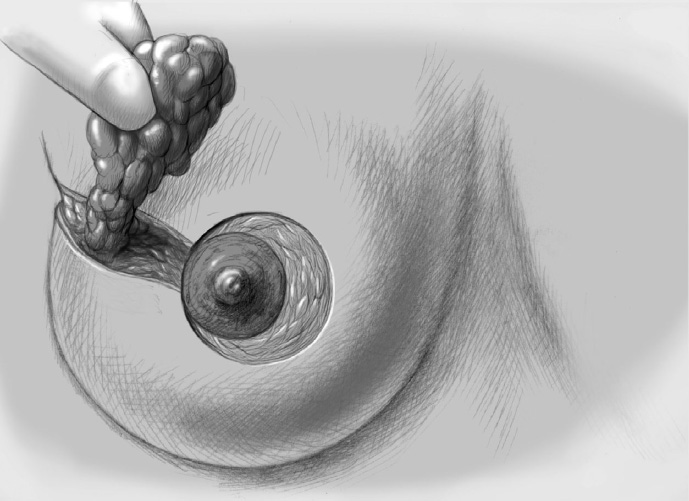

The basic decision on whether to use a complex oncoplastic technique is made when the skin is marked preoperatively, with the patient standing or sitting upright. Many surgeons successfully combine the B-plasty incision with periareolar de-epithelialization and excision of a straight or curved ellipse of peripheral skin (Chapter 1.3). When marking the periareolar deepithelialization pattern, an eccentric incision may be necessary to adjust the repositioning of the nipple–areola complex to the anticipated volume displacement.

The skin is incised superficially along the preoperative mark, initially with a scalpel. Many surgeons then proceed using electrocautery needle or scissors.

The periareolar skin is de-epithelialized. Here, too, there are various options. A strip of the most superficial skin layer can be excised with dissecting scissors applied flat or with a scalpel. It is important not to leave behind any surface containing squamous epithelium, but on the other hand the dermis and the important vascular layer beneath it must not be injured. The purpose of periareolar de-epithelialization is to recenter the nipple–areola complex and also to tailor excess skin to the new breast shape following extensive tumor resection.

Segmental excision of the area containing the tumor with resection margins as wide as possible to meet oncological criteria. Oncoplastic techniques should be used to achieve maximal oncological safety and avoid subsequent further resection.

Further resection is performed if necessary to ensure R0 status.

The former tumor region is marked with clips.

To cover the defect, the glandular lobes are mobilized from the adjacent parenchyma after subcutaneous dissection. The principle of intramammary lobe creation is to mobilize large parts of the breast (> 25%) either relative to the skin or relative to the pectoralis muscle. This “liberation” of the breast from one of its two planes of fixation allows adequate dissection and rotation of sufficient breast tissue. The Y-flap and rotation flap shown in Chapter 3.2.1 are examples of intramammary dissection.

When the breast is mobilized subcutaneously, it must be ensured that both the dissected skin layer and the breast tissue are sufficiently thick. For the layer of breast tissue, a minimum thickness of 1 cm is desirable. The ratio of base to length must also be considered.

The former tumor bed is marked with clips for optimized postoperative radiotherapy.

A Redon drain is placed prior to approximation of the breast lobes.

The mobilized breast lobes are rotated into the defect and approximated by interrupted sutures. Complete covering of the defect is desirable.

The skin is closed in two layers with recentering of the nipple–areola complex using interrupted sutures (Vicryl 3–0) according to the preoperative de-epithelialization pattern, which can be corrected at this time.

The skin is closed with an intracutaneous continuous monofilament suture.

Special Technique Complex Oncoplastic Breast-Conserving Surgery